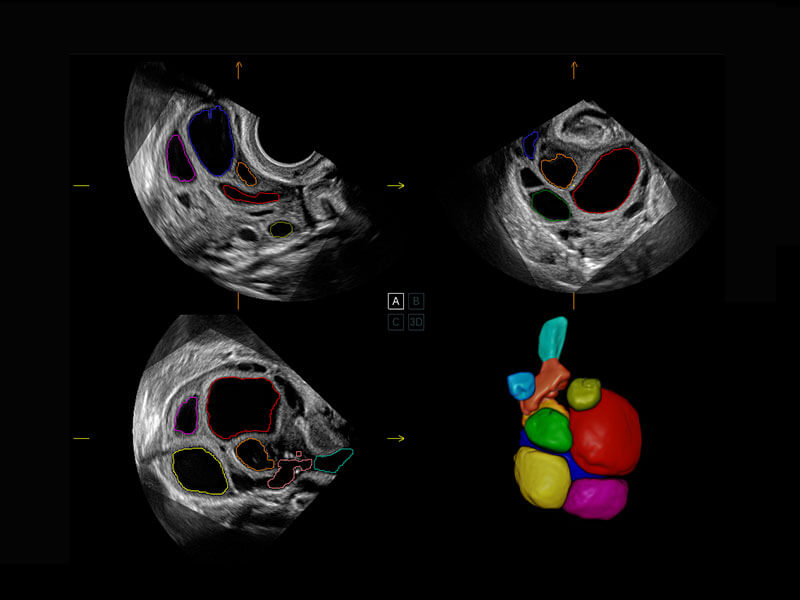

P60搭载一系列胎儿心脏成像技术,实现精细的胎儿心脏评估。

• 胎心容积成像